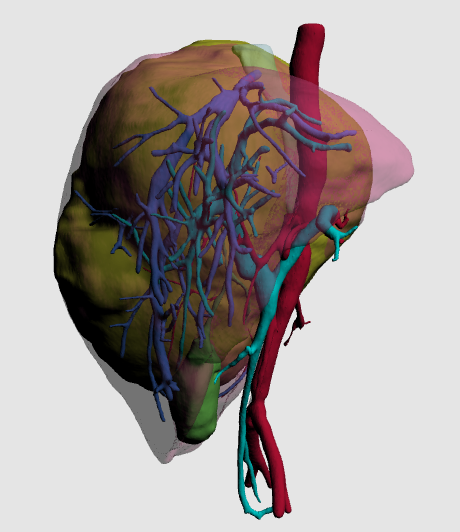

术前增强CT可见右肝巨大占位,约15x13x17cm,左肝推移,下腔静脉肝内段和中肝静脉受压,右肝静脉显示不清。

MDT讨论决定行肿瘤切除,术后行辅助化疗。手术难点:肿瘤巨大,侵犯、压迫大血管,解剖困难,术中出血风险高。对应策略:通过术前三维重建精确评估肿瘤与血管关系,制定手术计划。拟切除肿瘤所在的右半肝,剩余左半肝功能可代偿机体生理需要。